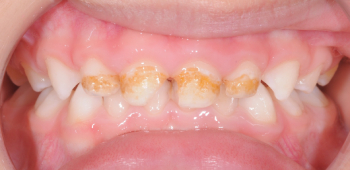

Antes: